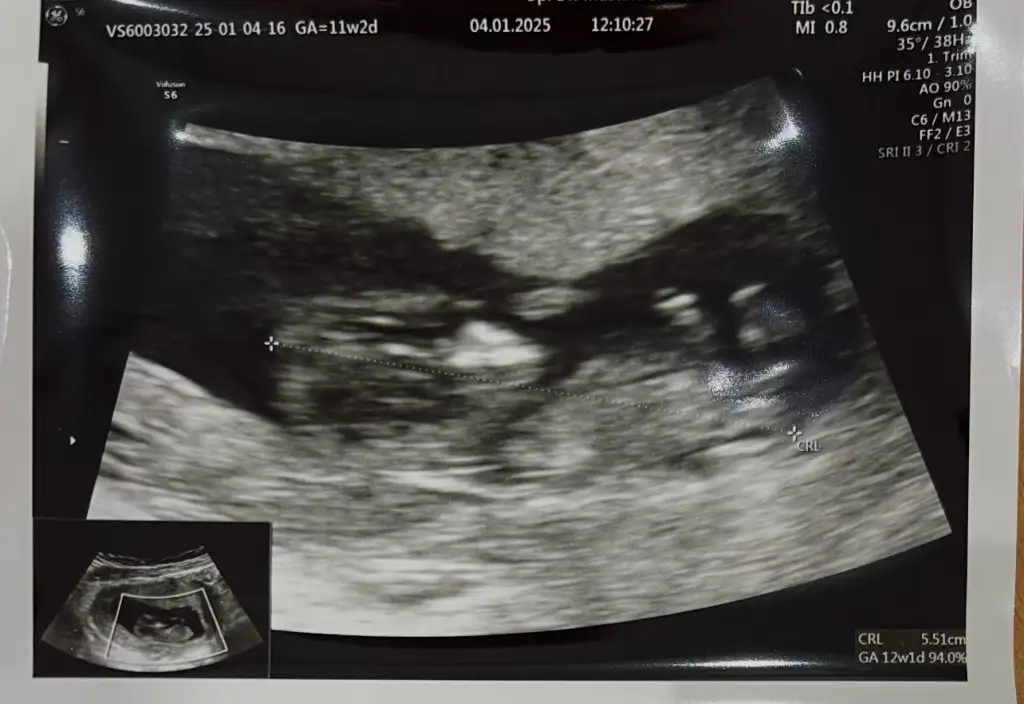

Merhaba benimde burda 12 hafta 5 gün bu haftalarda bacak arası sizdemi böylemiydi? Doktor erkeğe benziyor kızda ola bilir söyledi. Merak ediyorum böyle kız bebek genital organı olurmu?

Doktor bu gün kesin erkek söyledi 16 haftadayım.